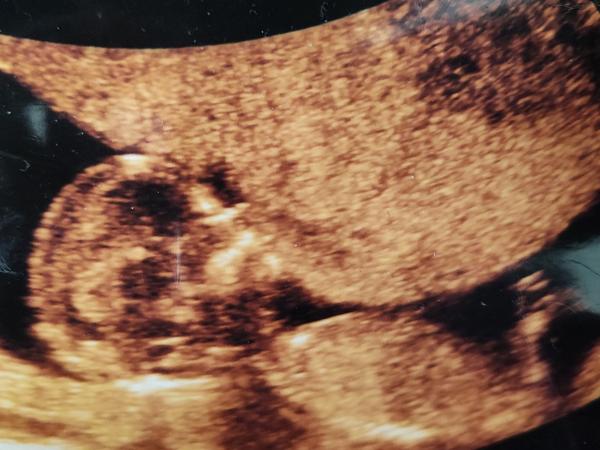

Poznáte pohlaví miminka podle utz z 1. i 2. trimestru?

Ahoj holky, jsem tu nová tak nevím moc jak to tu funguje. Poznáte podle ultrazvuku z 1. i 2. trimestru o jaké pohlaví se jedna? Můj doktor mi oznámil, ze mi nic ani nenaznaci pokud si nebude jistý alespoň na 90 % 🤷🏻♀️

Já bych řekla holcicka. Pohlavní hrbolek je spíše rovnoběžné s páteří. Já teď cekam 3ti holčičku (potvrzeno genetikou) a uz byl hodně podobný. Nemám ale foto.